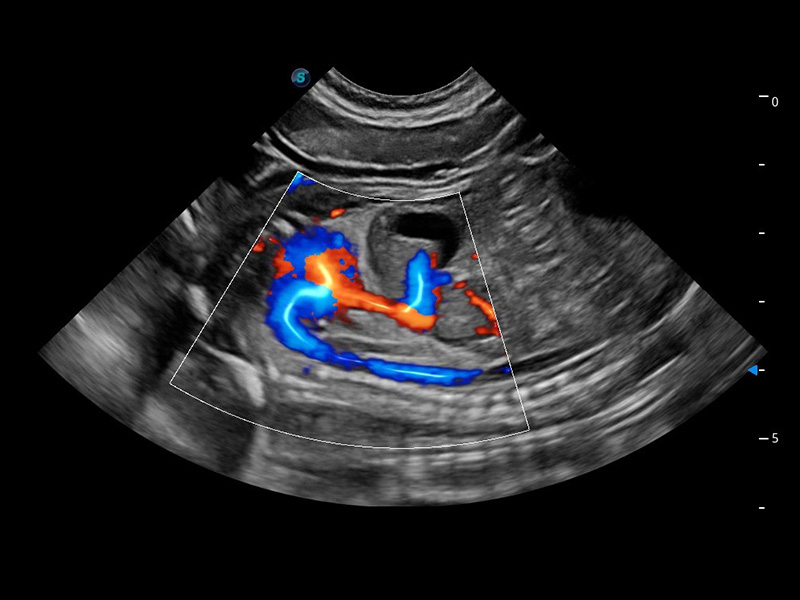

心脏解决方案

ProPet 60 配备了丰富的心脏探头群、先进的成像技术和专业的心脏测量工具,可帮助动物医生为不同体型和生理结构的动物提供心脏和心肌功能的全面评估。

• TDI 组织多普勒成像

实时用颜色表示心肌组织运动,观察和定量组织的运动情况,对快速检测与评估心肌的灌注和活性、电传导及心肌收缩和舒张功能等均能提供重要的诊断信息。

(犬)四腔心血流